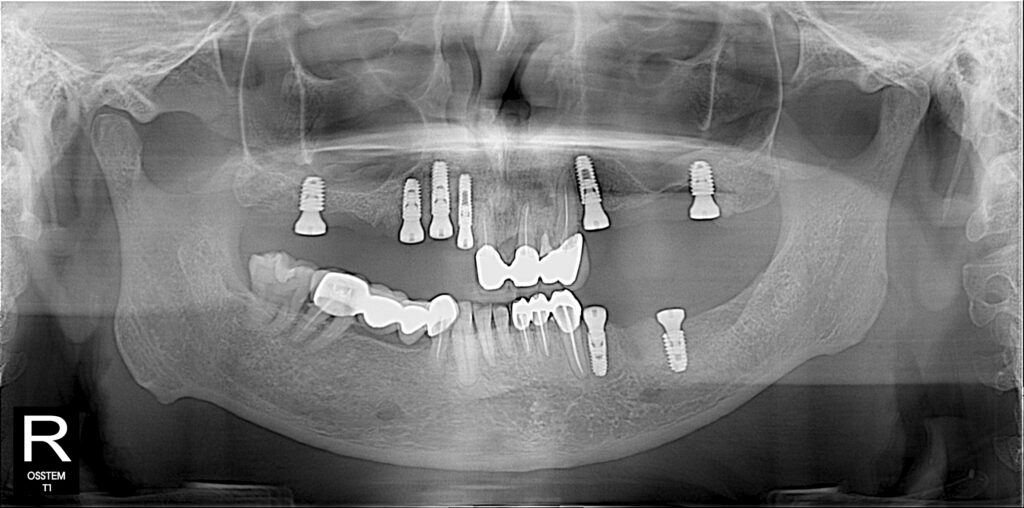

All-On-6 & 8 Dental Implant - Click

The All-on-6 dental implant technique is a full-arch restoration method where six implants are strategically placed in the jawbone to support a fixed prosthesis, such as a full set of teeth. This approach provides a permanent solution for patients with multiple missing teeth or complete tooth loss, offering better stability and load distribution compared to All-on-4. The posterior implants are often angled to maximize bone support and avoid anatomical structures like nerves or sinuses, reducing the need for bone grafting in many cases. It restores oral function and aesthetics, enhances patient confidence, and offers a durable, long-lasting alternative to removable dentures. The procedure involves implant placement, a healing period for osseointegration (typically 3-6 months), and the final attachment of the prosthesis, making it ideal for individuals with sufficient jawbone density seeking a reliable full-mouth restoration.

All-on-4 Dental Implant -Click

The All-on-4 is another option of dental implant for full-arch restoration method where four implants are strategically placed in the jawbone to support a fixed prosthesis, providing a permanent solution for total tooth loss or multiple missing teeth. The posterior implants are angled to maximize bone contact and avoid anatomical structures like sinuses or nerves, often eliminating the need for bone grafting. This technique offers a stable, cost-effective alternative to traditional implants, restoring oral function, aesthetics, and confidence. The procedure involves implant placement, a healing period for osseointegration, and attachment of a fixed prosthesis, making it suitable for patients with limited bone density seeking a reliable, long-lasting solution. Procedure duration 3 to 6 months. We always prefer to do this procedure with 3D guide.

All-On-4 Guided Implant surgery at out clinic

Computer-guided surgery uses the images from the patient’s cone beam CT scan to precisely plan implant treatment. Guided surgery software allows us to visualize and manipulate images of the patient’s jawbone and the surrounding tissue, giving the opportunity to plan the most accurate approach to treatment.

All-on – 4 is more complicated dental implant procedure and need to be well planned and precise. Due age of the patients its sometimes difficult to bear lengthy surgical procedure. Planning with #D Guide minimize the operation time and reduce post operative complications.